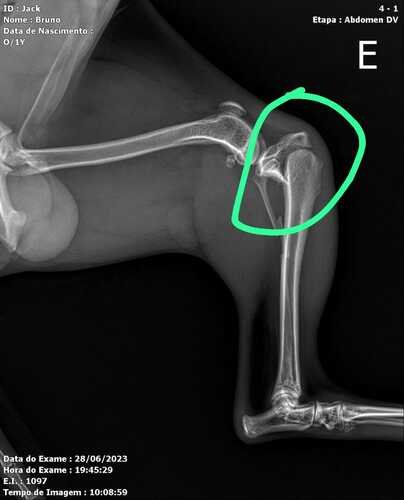

Eu sou Bruno, pai do Jake que é um doguinho de 11 meses muito alegre, carinhoso e amoroso, e muito muito espuleta, no dia 28/06/2023 Jake se machucou sozinho, e acabou fraturando as duas pernas traseiras, sendo assim precisando passar por cirurgia.Por isso estamos aqui pedindo ajuda pra quem puder doar qualquer valor para que o Jake volte a correr e brincar